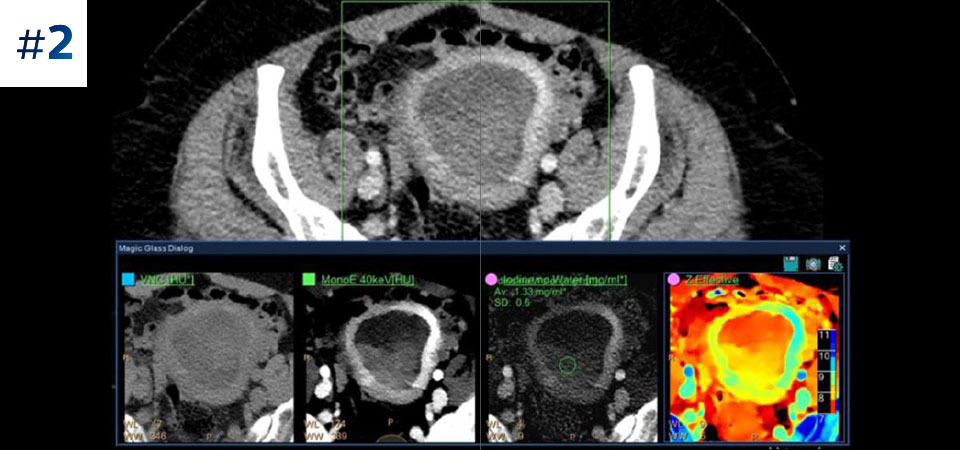

Observez la différence entre le scanner à détection spectrale et le scanner classique

Découvrez les avantages du scanner à détection spectrale